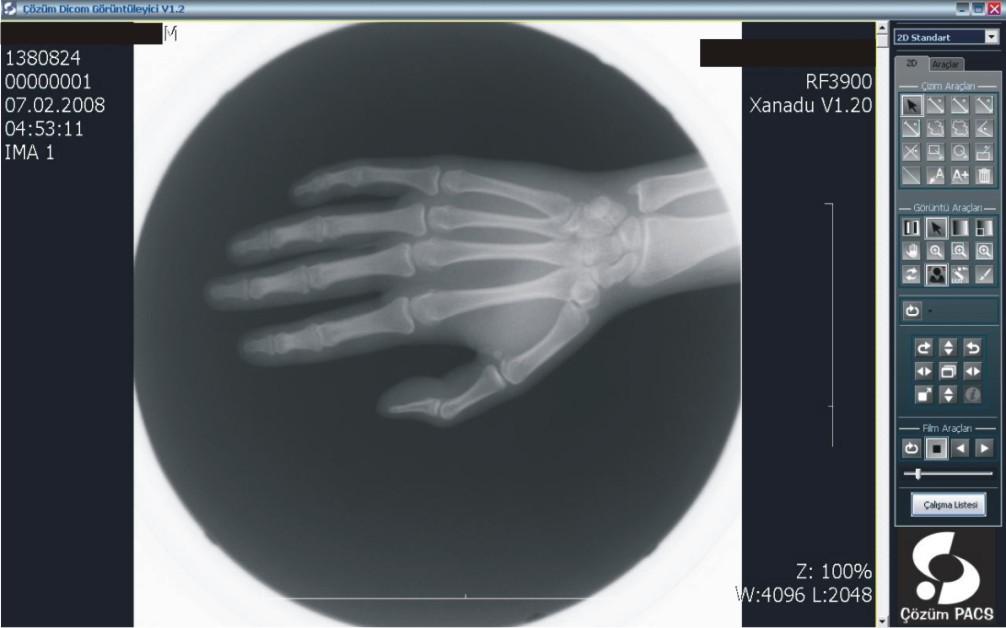

PACS (Picture Archiving And Communication System) alım işlemlerini sonuçlandıran hastane yönetimi “dijital hastane” olma yolunda emin adımlarla ilerliyor. Konu ile ilgili olarak, Başhekim Yardımcısı Dr. Muhammet Özgehan sistemin sağlayacağı avantajları üzerine Dergimize kısa açıklamalarda bulundu;

Hastanemizde bilgi yönetim sistemi olarak Çözüm HBYS'yi (Hastane Bilgi Yönetim Sistemi) kullanıyoruz. Güçlü bir entegrasyon sağlamak adına uluslararası standartlara haiz, tamamı Türk mühendislerine ait tek PACS olma özelliğindeki Çözüm PACS'ı tercih ettik.

PACS ile, dijital olarak elde edilen panoramik ve lokal radyolojik görüntüler (ultrasonografi, doppler, magnetik rezonans, tomografi v.b. cihazlardan elde edilen veriler) çevrimiçi ortamlarda dijital arşivleme yöntemleriyle saklanıyor. Kayıpsız bir şekilde, hızlı ve güven içinde saklanan bu görüntüler, gerektiğinde istemcide yeniden görüntülenerek kullanılabiliyor.

Merkezi veri tabanında bilgilerin depolanması ile oluşan dijital arşiv (görüntüler üzerinde işlem yapmaya izin verecek şekilde yüksek çözünürlükte saklandığı için ölçüm ve tanıya ilişkin işlemler kolaylıkla yapılabiliyor), bilgilerin yeniden kullanılmasını arşivlenen bilgilerin modern tanı yöntemleri ile incelenmesini sağlıyor. Dijital görüntüler üzerinde işlem ve ölçüm yapılabiliyor. Görüntüler ve raporların her an, her yerde (tüm iş istasyonları üzerinden sorgulama yapılarak) ulaşılabilir olmasına ve görüntü işleme ve ölçüm (mesafe, açı, uzunluk, yoğunluk) yapılabilmesine imkan sağlıyor.

PACS, tanı ve teşhislerde daha doğru sonuçlar elde edilmesini sağlayarak  sonuçları  yorumlama ve raporlama süresini hızlandırıyor. Görüntülerin karşılaştırılması ve radyolojik bulguların geriye dönük değerlendirilmesi, karşılaştırmalı raporların incelenmesi, hekimin hastalığın gelişim sürecini daha iyi kavramasını ve doğru teşhisi daha hızlı bir şekilde koyabilmesini sağlıyor. Yedeklenen PACS görüntüleri istenildiğinde hastalara CD-DVD halinde veriliyor.